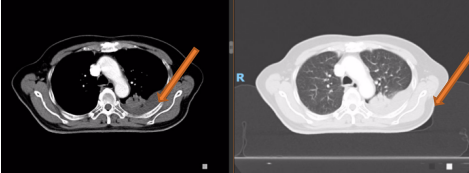

胸部平扫+增强CT(2020-08-27):食道中段管壁增厚,上下累及约4.5厘米(约胸5/6椎间隙水平至胸8椎体上缘水平),增强后可见轻度强化,隆突下见境界不清淋巴结。左肺上叶尖后段及相邻左肺下叶背段交界处见团块状直径约2.5厘米软组织密度灶,边缘可见毛刺,左侧胸腔积液,左下肺膨胀不全。右肺下叶见少许条状影。结论:1、食管癌。2、左肺上叶尖后段病灶,符合肺癌。左侧胸腔积液,左下肺膨胀不全。

2022-03-28 PET-CT:1、食管癌放化疗后,食管胸中段管壁不规则增厚伴结节状代谢增高,与上次(2021-10-28)PET/CT检查对比,病灶代谢较前明显增高,考虑为肿瘤复发病灶。2、左肺癌放疗后及靶向药治疗后,原左肺上叶团块状高代谢“肿瘤灶”,现范围较前稍缩小,代谢较前稍减低,考虑为治疗后改变(肿瘤完全活性受抑,伴少许炎性反应可能)。